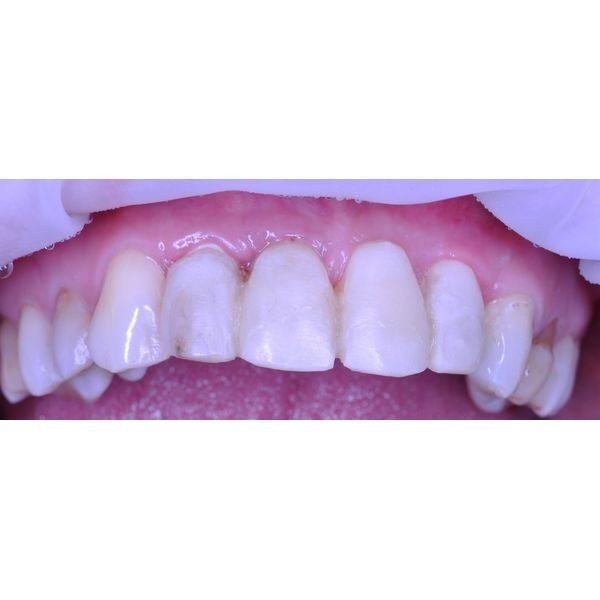

Зубы 1.1, 1.2, 2.2 удалили, сразу же установили в раны имплантаты и зафиксировали временный пластмассовый протез. С ним пациентка ходила 5 месяцев.

Ей также смоделировали десневую манжету, на основе чего изготовили циркониевый мостовидный протез с керамической облицовкой.

Первые несколько дней после процедуры женщина отмечала небольшую болезненность, однако благодаря временному пластмассовому протезу социальная жизнь не пострадала.

На следующем приёме ей удалили временный протез и установили циркониевый мост.